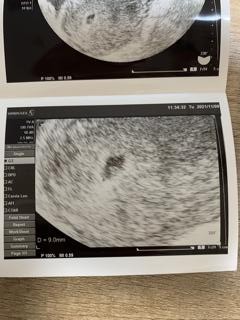

最終生理から5w2dの今日、初診で9㍉の胎嚢と卵黄囊が見えました♡

頑張れ赤ちゃん♡